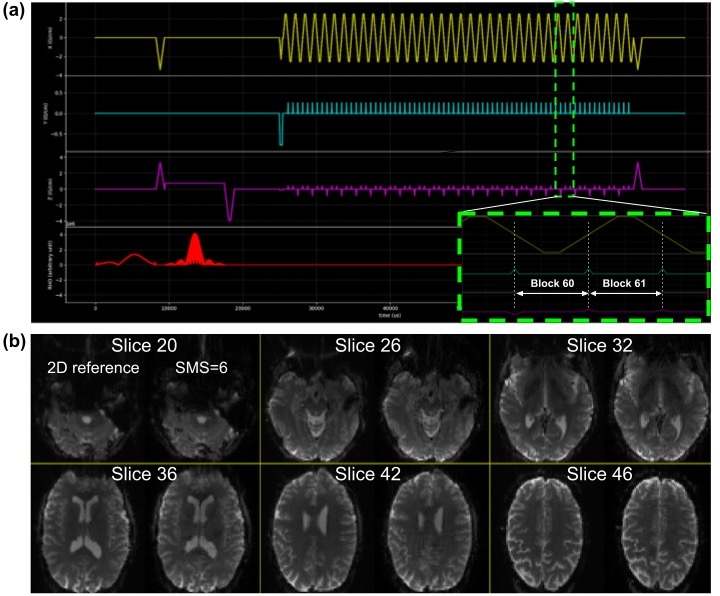

We implemented a BOLD SMS-EPI sequence with parameters that closely match the ABCD protocol21: 2.4 mm isotropic resolution, 90x90 matrix size, 60 slices without gaps, SMS factor 6, 1x6z2 CAIPI sampling pattern,22 TR 0.8 s, partial Fourier factor 0.8. We created the various sequence events, and assembled the Pulseq sequence object, using the MATLAB Pulseq toolbox. The MATLAB scripts are freely and openly available on Github,23 enabling users to modify the acquisition parameters to suit their own needs.

Figure 5(a) shows the timing diagram for one sequence TR, which consists of fat saturation using a minimum-phase Shinnar-Le Roux (SLR) pulse,24 SMS excitation using SLR sub-pulses with phase offsets following the scheme by Wong,25 and ramp-sampled EPI readout. To reduce the risk of PNS during the EPI train, we derated the slew rate to ensure that the predicted PNS, based on the nerve impulse response model19 stays below 80% of the stimulation limit (normal mode). The sequence is RF-spoiled to suppress steady-state signal contributions from spin- and stimulated-echo pathways.26

Image reconstruction

To reconstruct images from the acquired raw (k-space) SMS-EPI data, the user is free to choose from several available image reconstruction pipelines. The HarmonizedMRI development team has implemented both 3D SENSE27 and slice GRAPPA28 SMS-EPI reconstructions in MATLAB that are part of the QA protocol described below. Other community-developed implementations are also available.29–33 Figure 5(b) shows the results of reconstructing Pulseq SMS-EPI data using 3D SENSE27 implemented in BART.32 Figure 6 demonstrates that our Pulseq protocol achieves similar image contrast and overall image quality as the matched product protocols.